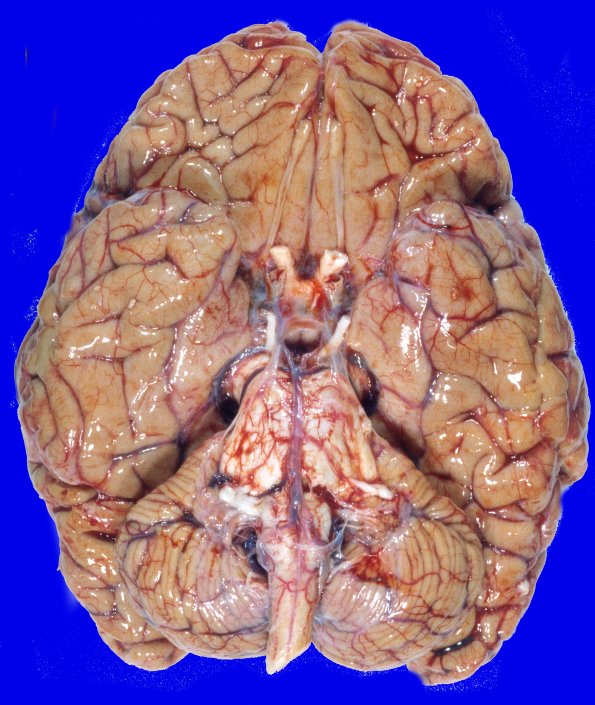

The dorsal and ventral view of her brain show cerebral and cerebellar atrophy.